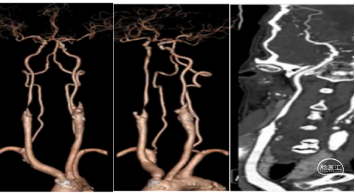

典型病例1: 患者,mshq 男性,44岁,“突发右侧上下肢无力,言语含糊”,溶栓后肢体肌力4-级,搀扶行走。经基层医院静脉溶栓后转入我院。外院核磁显示:左侧侧脑室后角梗塞。MRA显示:C4-C5段以远血管显影浅淡。

转入我科后,患者肢体较溶栓后略有加重,右下肢肌力3级,上肢2级。造影显示:左侧颈内动脉C1段呈火苗样窜动,提示:远端闭塞可能。说明病情在持续加重,可能为血栓堆积闭塞了血管。

颈内动脉C1~C3血管迂曲呈u型、S型改变。血液滞留。泥鳅导丝、130cm西蒙导管、Neuron MAX长鞘同轴到达C1段到达S迂曲。